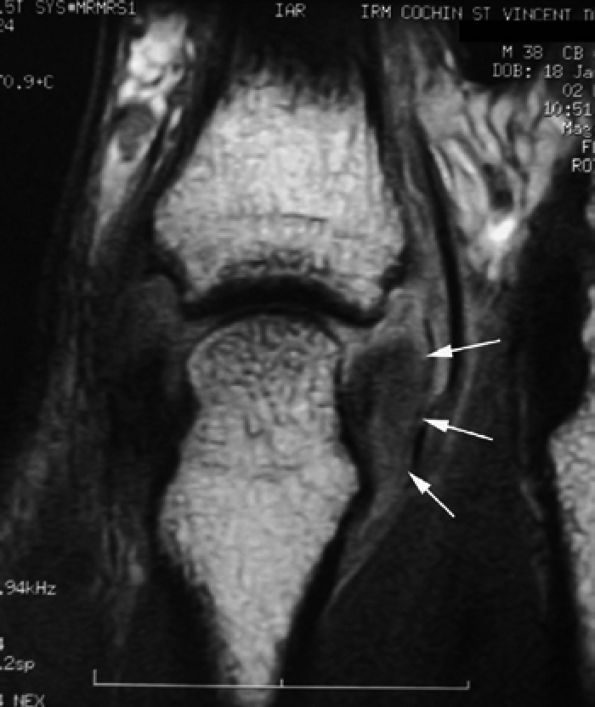

FIGURE 11.11 ● Tear of the radial collateral ligament (RCL) of the fifth metacarpophalangeal joint is shown on this coronal post-contrast T1-weighted image. The distal insertion of the RCL is proximally retracted and thickened (arrows).

|